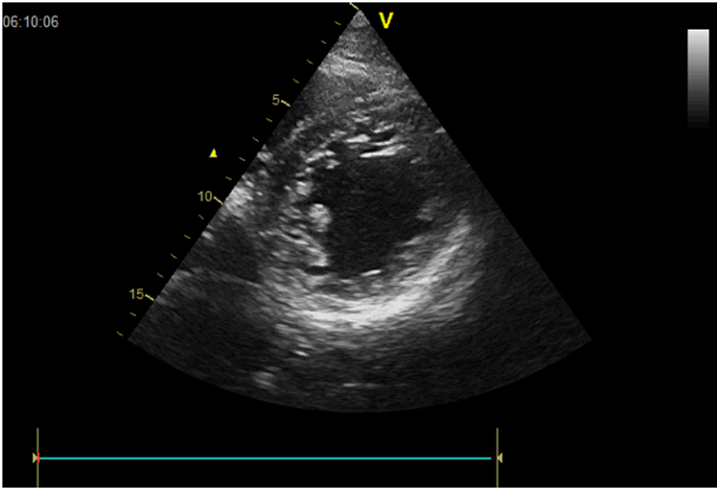

Echocardiography confirmed a severely depressed left ventricular ejection fraction (LVEF) of 20%, with a markedly dilated left ventricle, prominent trabeculations, spontaneous echogenic contrast, and an apical thrombus—all features raising suspicion of a left ventricular non-compaction cardiomyopathy (LVNC) (figure 2 and 3)

Figure 3: short axe Vue showing the Left ventricle trabeculations